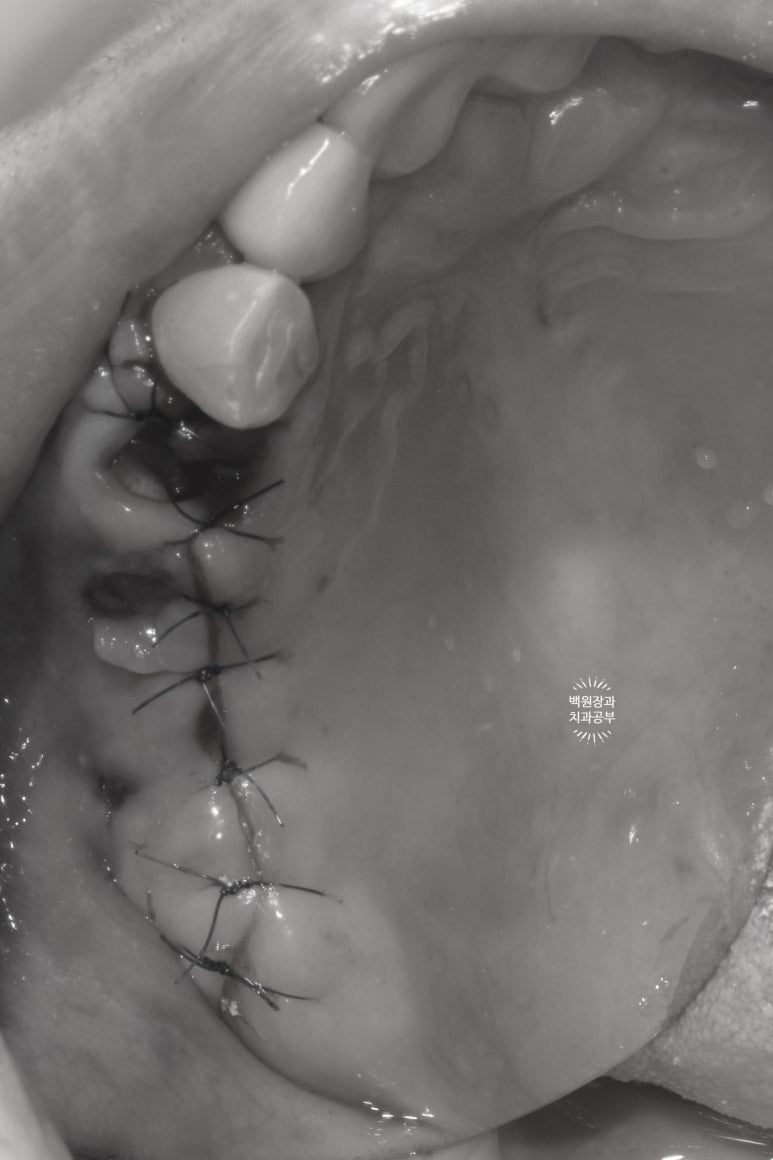

덴티움 뼈이식재를 이용한 치조제 보존술을 합니다.

해당 임플란트와 자연치를 제거하고 너무나 큰 빈 공간에 뼈이식을 하게 됩니다.

그리고 덴티움의 시그니처 뼈이식재인 osteon III를 사용해서 동시 뼈이식을 계획했어요.

임플란트 재수술의 기초는 반드시 임플란트 제거와 동시에 뼈이식을 함으로써 시작되는데요,

보시다시피 엄청나게 큰 웅덩이가 세개나 있는 것을 보실 수 있을거에요.

제가 애정하는 덴티움 (제노스) 사의 Osteon III 1.0cc 합성골을 이용하여 넉넉하게 뼈이식을 해주었습니다.

저희 치과의사는 이를 뽑으면서 뼈이식을 하는 행위를 치조제보존술이라고 부릅니다.

그리고 '반드시' 덴티움 뼈이식재 상방에 덴티움 차폐막을 덮어주어야 합니다.

차폐막은 주변 잇몸 조직으로부터 뼈이식재료들이 침범당하지 않고 오롯이 뼈가 되도록 도와주는 역할을 합니다.

꽤나 깔끔하게 꿰매진 것을 보실 수 있을겁니다 :)